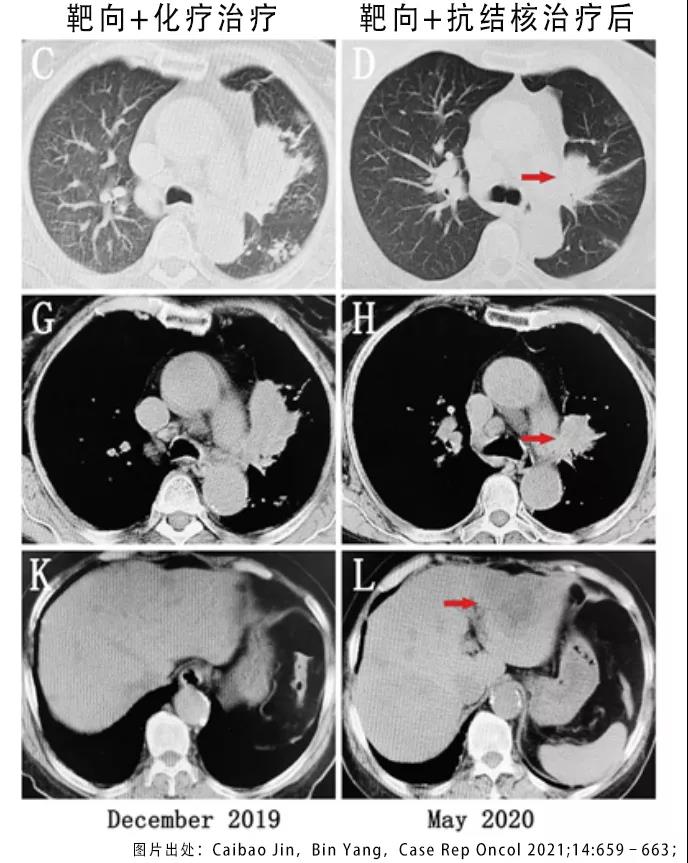

2020年1月,在确定为肺结核之后,患者接受了异烟肼、利福平、吡嗪酰胺和乙胺丁醇组成的HRZE方案治疗。同时继续使用靶向药物治疗肺癌。2个月以后,胸部和腹部CT检查证实肺部肿块明显缩小,但是肝部和肾上腺的转移灶开始增大了。

图2 靶向联合化疗及靶向联合抗结核治疗后的CT检查 图2 靶向联合化疗及靶向联合抗结核治疗后的CT检查